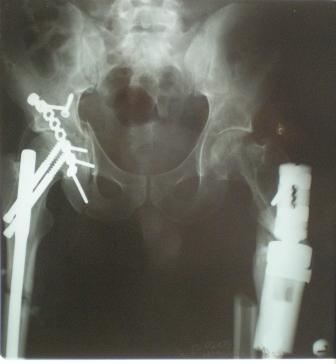

Глубокоуважаемые коллеги! Благодарю за полезные советы, которые нам очень помогли в выборе оперативной тактики пациента. 13.02.08 мы выполнили первый этап оперативного лечения этого больного. Вначале зафиксировали левое бедро АВФ Гофмана

(главный травматолог области достал из каких-то «анналов», первый раз в жизни увидел этот аппарат в живую). После наложения «ДРУ Челнокова» выполнили ЗИО правого бедра реконструктивным штифтом Chm. Далее уложили пациента на левый бок и выполнили остеосинтез вертлужной впадины. Ограничились задне-латеральным доступом без отсечения вертела, чтобы не утяжелять операцию. Результат прилагается.

Следующим этапом планируем выполнить ЗИО левого бедра.

1. укорочение левой н\конечности составляет 3 см. Необходимо ли думать об этом сейчас, или вернуться к устранению укорочения после консолидации перелома?

2. сохраняется некоторое смещение переднего отдела вертлужной впадины, нужно ли его устранить?

Я тобой гордюсь! Тюменские тазы в надежных руках все вроде отлично.

И смещение передней колонны вроде бы не критично.